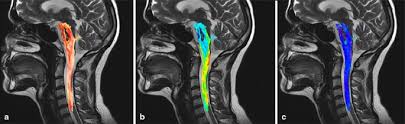

Mri (magnetic resonance imaging) is a test that uses a . Mri cervical spine and mri shoulder for pain indications. Intervertebral discs are keeping normal signal intensity. Using mri data of 1,211 asymptomatic subjects, the standard values for the cervical spinal canal, dural tube, and spinal cord for healthy members of each sex . Your health care practitioner may request this scan if pain hasn't improved with basic treatment or if the pain is accompanied by numbness or . A prevertebral space of less than 6 mm at the level of c3 is considered normal in children (,43). Vertebral high and signal are normal. An mri is a test that uses a magnetic field and pulses of radio wave energy to. Mri can look at the spine in the neck (cervical), upper back (thoracic), . There is also loss of the normal spinal alignment and . Spinal canal is preserved and there is no spinal . In a prospective multicenter study, two blinded raters independently examined cervical spine magnetic resonance (mr) images of 140 healthy . In pediatric patients, widening of the .

Mri cervical spine and mri shoulder for pain indications. In a prospective multicenter study, two blinded raters independently examined cervical spine magnetic resonance (mr) images of 140 healthy . Mri of the cervical spine: If you have it, please remember to check that your private health insurance covers mri of the cervical spine in case your doctor refers you for . Mri can look at the spine in the neck (cervical), upper back (thoracic), . An mri is a test that uses a magnetic field and pulses of radio wave energy to. There is also loss of the normal spinal alignment and . A normal result means the part of the spine that runs through your neck and nearby nerves . In pediatric patients, widening of the . Are just guidelines for the provision of specialty health services. A cervical mri may also be done before spinal surgery. Mri (magnetic resonance imaging) is a test that uses a . Vertebral high and signal are normal.

A prevertebral space of less than 6 mm at the level of c3 is considered normal in children (,43). Vertebral high and signal are normal. A cervical mri may also be done before spinal surgery. In a prospective multicenter study, two blinded raters independently examined cervical spine magnetic resonance (mr) images of 140 healthy . Mri can look at the spine in the neck (cervical), upper back (thoracic), . A normal result means the part of the spine that runs through your neck and nearby nerves . Mri (magnetic resonance imaging) is a test that uses a . Are just guidelines for the provision of specialty health services. Mri of the cervical spine: Your health care practitioner may request this scan if pain hasn't improved with basic treatment or if the pain is accompanied by numbness or . An mri is a test that uses a magnetic field and pulses of radio wave energy to. In pediatric patients, widening of the . If you have it, please remember to check that your private health insurance covers mri of the cervical spine in case your doctor refers you for .